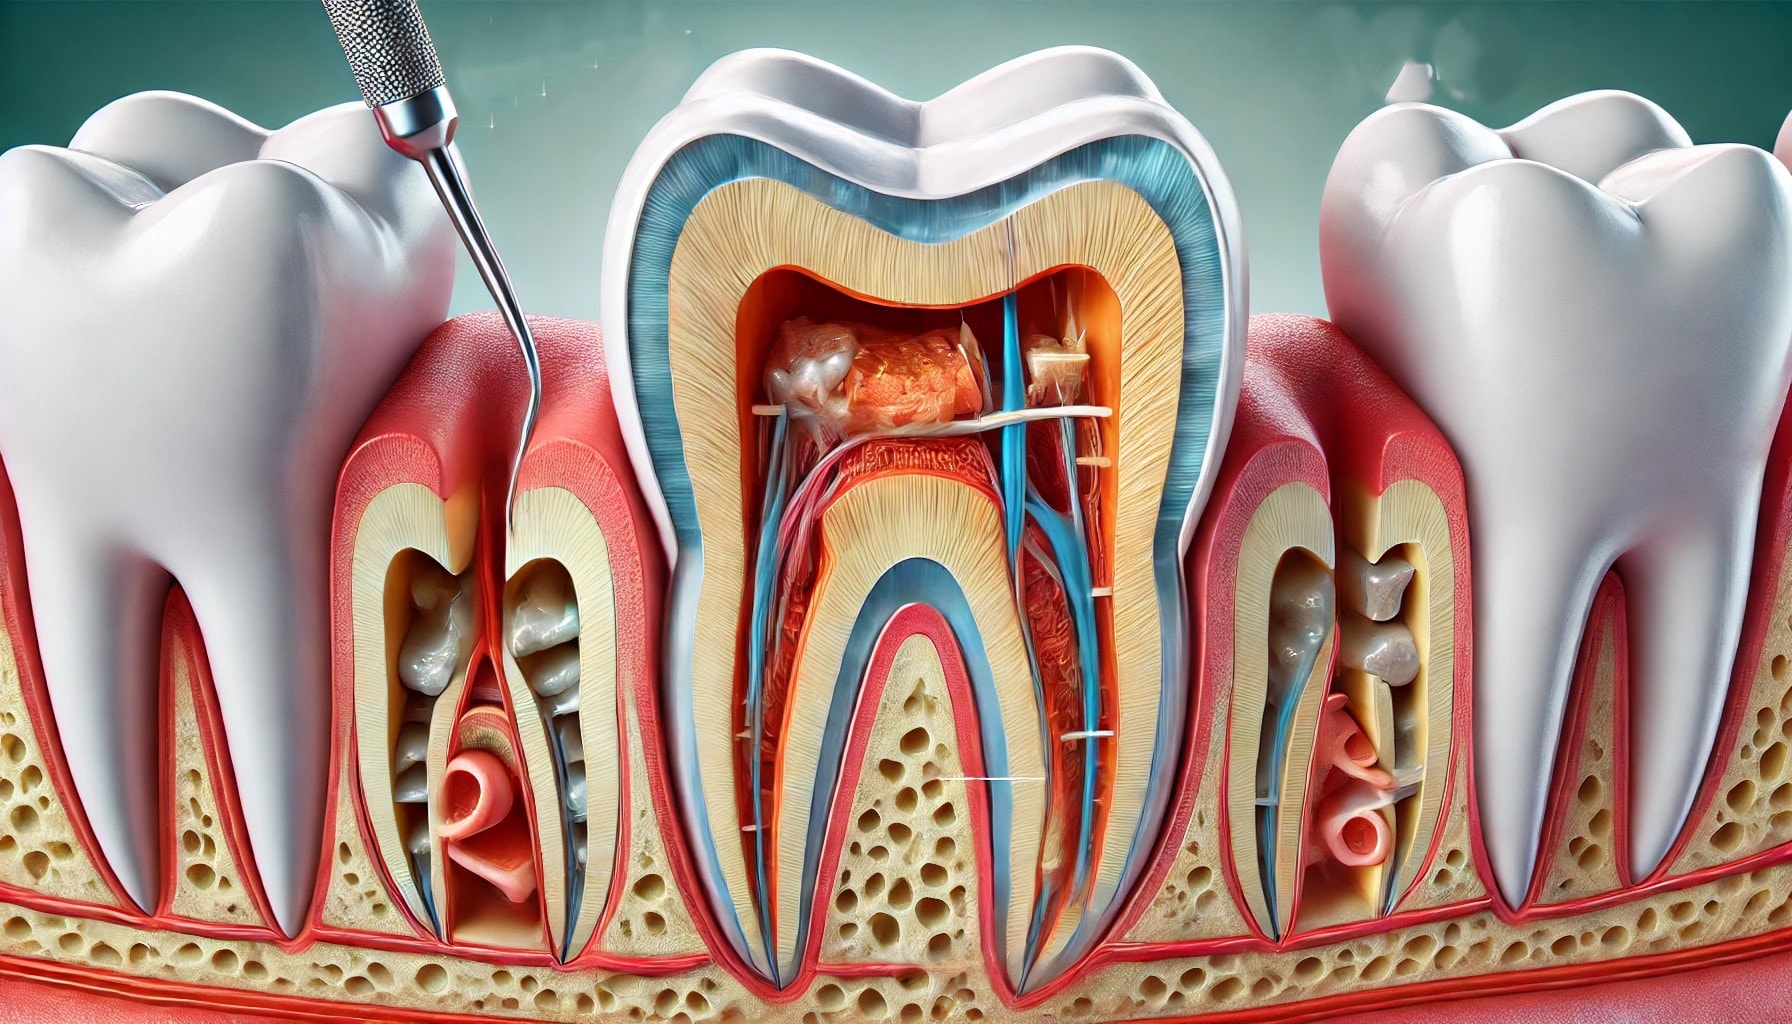

Når en tann har store fyllinger, kan den være utsatt for ytterligere skade eller infeksjon. En rotfylling blir derfor en avgjørende behandling for å bevare tannen og forhindre mer alvorlige problemer. Over tid kan fyllinger svekkes av belastning eller nedbrytning, noe som gir bakterier muligheten til å trenge inn i tannen. Dette kan føre til infeksjon i tannpulpa, vevet som omgir tannen. Gjennom rotfylling fjernes den infiserte pulpaen, og tannen blir renset for bakterier.

Etter at rotkanalene er renset og desinfisert, fylles de med en biokompatibel materiale som hindrer videre infeksjon og bidrar til å bevare tennens strukturelle integritet. Behandlingen gir tannen ny styrke og reduserer risikoen for brudd. For tenner med store fyllinger kan rotfylling være en kostnadseffektiv løsning, da det ofte er mer økonomisk å bevare en eksisterende tann enn å erstatte den med et implantat eller tannbro i fremtiden.

Når det gjelder rotfylling, er det viktig å forstå både behandlingsprosessen og de tilknyttede kostnadene. Behandlingen starter vanligvis med en grundig undersøkelse av tannlegen, som kan inkludere røntgenbilder for å vurdere omfanget av skaden.

Selve prosedyren innebærer å bedøve det berørte området for å minimere ubehag, før tannlegen fjerner den infiserte tannpulpaen og rengjør rotkanalene. Deretter fylles kanalene med et biokompatibelt materiale. Behandlingen kan ta fra 1-2 timer avhengig av kompleksiteten.